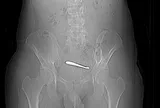

Theo thời gian, tê lan sang ngón áp út, lực bàn tay giảm dần, cầm nắm không chắc. Khi đến khám chuyên khoa, qua thăm khám lâm sàng và siêu âm thần kinh, bác sĩ phát hiện dây thần kinh trụ tại rãnh khuỷu tăng kích thước rõ rệt, có dấu hiệu bị chèn ép.

Các bác sĩ cho biết, dây thần kinh trụ đi qua rãnh ròng rọc phía trong khuỷu tay - vị trí dễ bị tổn thương. Hội chứng chèn ép thần kinh trụ đoạn khuỷu là bệnh lý thần kinh ngoại biên khá phổ biến ở chi trên, chỉ đứng sau hội chứng ống cổ tay. Nếu chèn ép kéo dài, người bệnh có thể yếu tay, teo cơ bàn tay và nguy cơ mất chức năng không hồi phục.

Với trường hợp này, bệnh nhân được chỉ định phẫu thuật giải phóng và chuyển vị thần kinh trụ nhằm giảm áp lực. Sau phẫu thuật, tình trạng tê bì giảm rõ rệt, lực bàn tay cải thiện dần, hiện người bệnh đã sinh hoạt gần như bình thường.